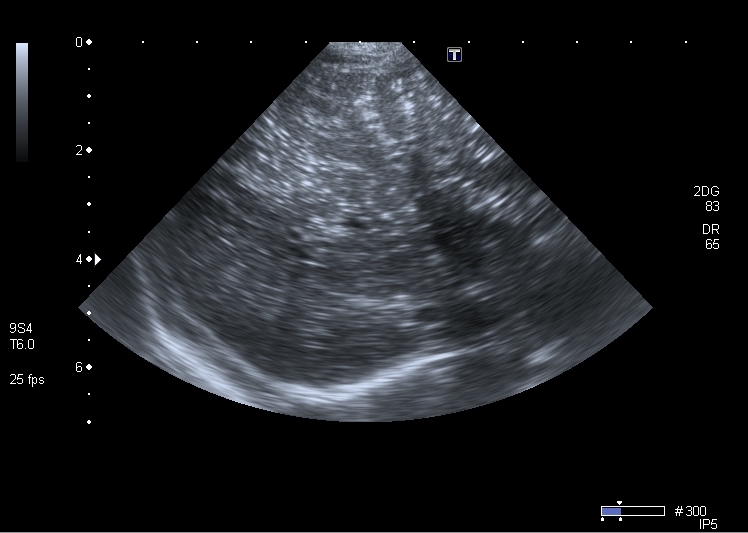

Хочу продолжить дискуссию, повод для этого - сегодняшний пациент 1 года 4 месяцев с клиникой кишечной инфекции и подозрением на инвагинацию. Инвагината не нашёл, но зато при УЗИ выявлены следующие изменения в печени

Кроме того был выражен феномен спонтанного контрастирования кровотока в портальной системе (пузырьки газа?). На рентгенограмме - единичные горизонтальные уровни в тонкой кишке, интерстициального пневматоза стенки газа в проекции портальной системы нет.

Лично наблюдал газ в портальной системе у новорожденных детей с некротическим энтероколитом, они действительно лечились в отелении реанимации и находились в крайне тяжёлом состоянии. Данный ребёнок не производил впечатление умирающего и чувствовал себя отностиельно неплохо. В общем анализе крови - небольшой сдвиг влево и всё. Петли тонкой кишки при УЗИ незначительно расширены, с внутрипросветным депонированием жидкого содержимого, перистальтика усилена, газы отходят. Свободная жидкость в брюшной полости на момент исследования в брюшной полости в небольшом количестве

У ребёнка в анамнезе запоры.В последние дни ребёнка интенсивно клизмили. Был зловонный пенистый стул, метеоризм. Но впечатления о том, что у него разваливается стенка кишки или кишка настолько раздулась, что возник интестициальный пневматоз нет. Есть ли другие варианты эхогенных включений в портальной системе?